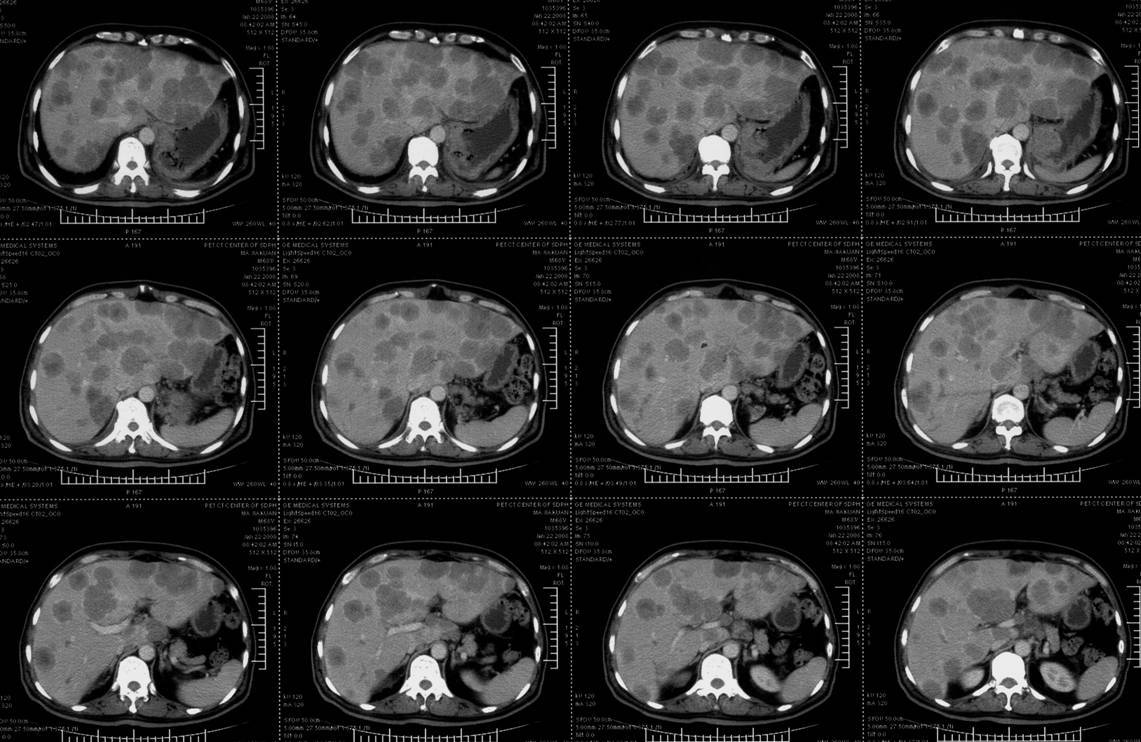

肝脏转移瘤ct1 mhc,胃癌(147580) 胃癌肝转移

病例肝转移瘤1例ct影像表现–影像ppt